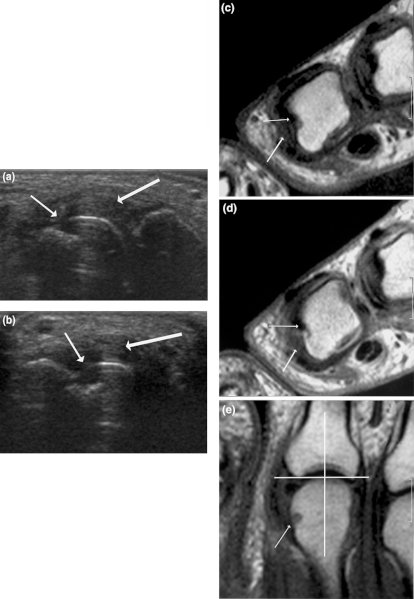

Arthritic changes – Arthritis is related to a condition of painful joints due to inflammation or swelling. A type of arthritis is rheumatoid arthritis, it is an autoimmune disease where the immune system attacks the joints, starting with the lining of joints. Rheumatoid arthritis is heavily related to lung problems, about 80% of arthritic patients have lung-related issues, making it the second leading cause of death with rheumatoid arthritis patients. Rheumatoid arthritis caused lung problems are most commonly extra-articular i.e., outside of the joints and involves pulmonary nodules; damage to the lung airways, pleural effusion and interstitial lung disease. In rheumatoid arthritis associated interstitial lung disease the auto-immune system gets over active and attacks the lungs and causes scarring. With time, the scarring build-up leads to difficulty breathing and reduced lung function.